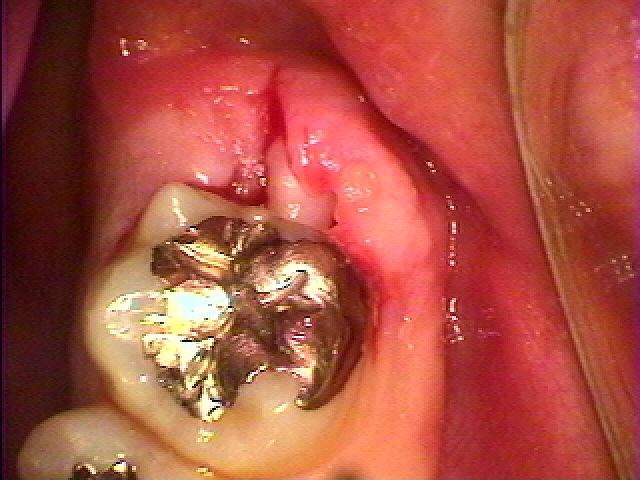

少し歯茎が腫れているのがわかるでしょうか?

親知らずが少し見えます